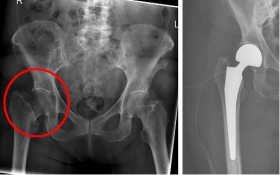

In older age and with stronger displacement of the fracture can be done by a duo-head prosthesis. Here only the femoral head is replaced, the hip socket is preserved. In case of simultaneous hip arthrosis, a total endoprosthesis (hip replacement) with replacement of the acetabular cup can be used.

Oberschenkel 4

Picture: In this case, there was already a wear of the hip joint and the affected patient was relatively young, so that a cement-free total endoprosthesis (TEP) of the hip was selected for the treatment of the femoral neck fracture. Here, in addition to the femoral head, the acetabular cup was replaced by an implant.